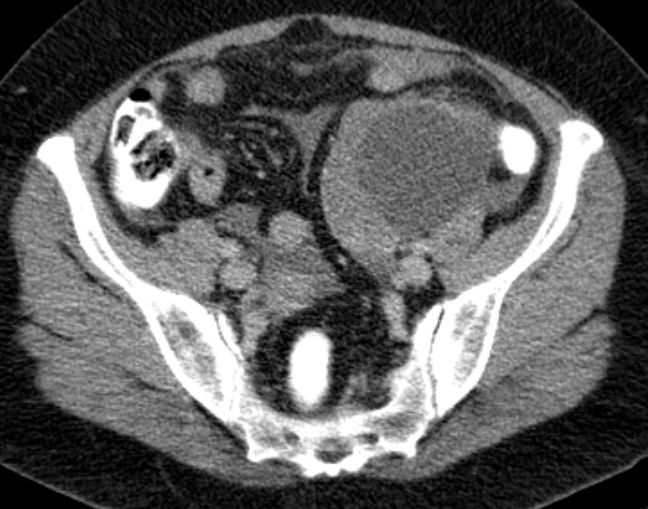

malignes Teratom 58-jährige Frau mit einen malignen Teratom mit Abszedierung und akuter Peritonitis.

Tumormarker AFP 2,86; CEA 2,27; CA 19.9 = 33 060 (N < 37!)

Makroskopie: Mehrteilige, maximal 10,9 cm messende, knotige, gelblichbräunliche und z. T. bröckelig zerfallende Gewebeproben.